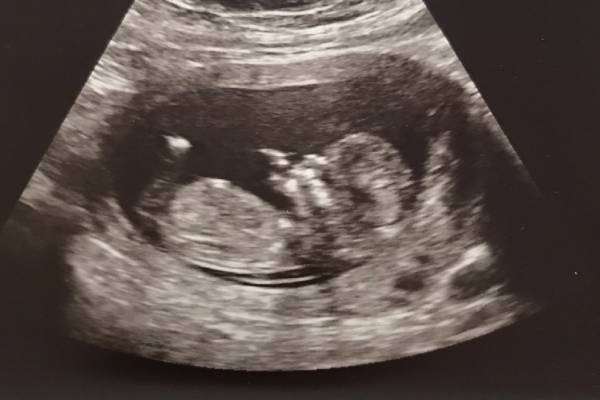

A Nuchal Translucency (NT) Scan in Pune is a first-trimester prenatal ultrasound that measures the translucent (fluid) space behind your baby’s neck. All fetuses have this fluid, but in some cases the fluid space is thicker than usual, which may indicate a higher probability of chromosomal or structural abnormalities.

This NT Scan in Pune is safe, non-invasive, and painless. The procedure uses high-resolution ultrasound and is generally handled by trained fetal medicine specialists or certified sonographers, such as at Dr. Deepti Mittal’s clinic, ensuring reliable results and proper interpretation.

An NT Scan gives important insight into your baby’s early development and risk for certain chromosomal conditions. Your report will show a measurement in millimetres along with a risk estimate. A normal NT value, usually below 2.5–3.0 mm, is generally reassuring and indicates a low risk, though it doesn’t guarantee that everything is perfect. If the NT value is higher than average, it may suggest a slightly increased risk. This does not mean your baby definitely has a problem—it simply signals the need for further evaluation.